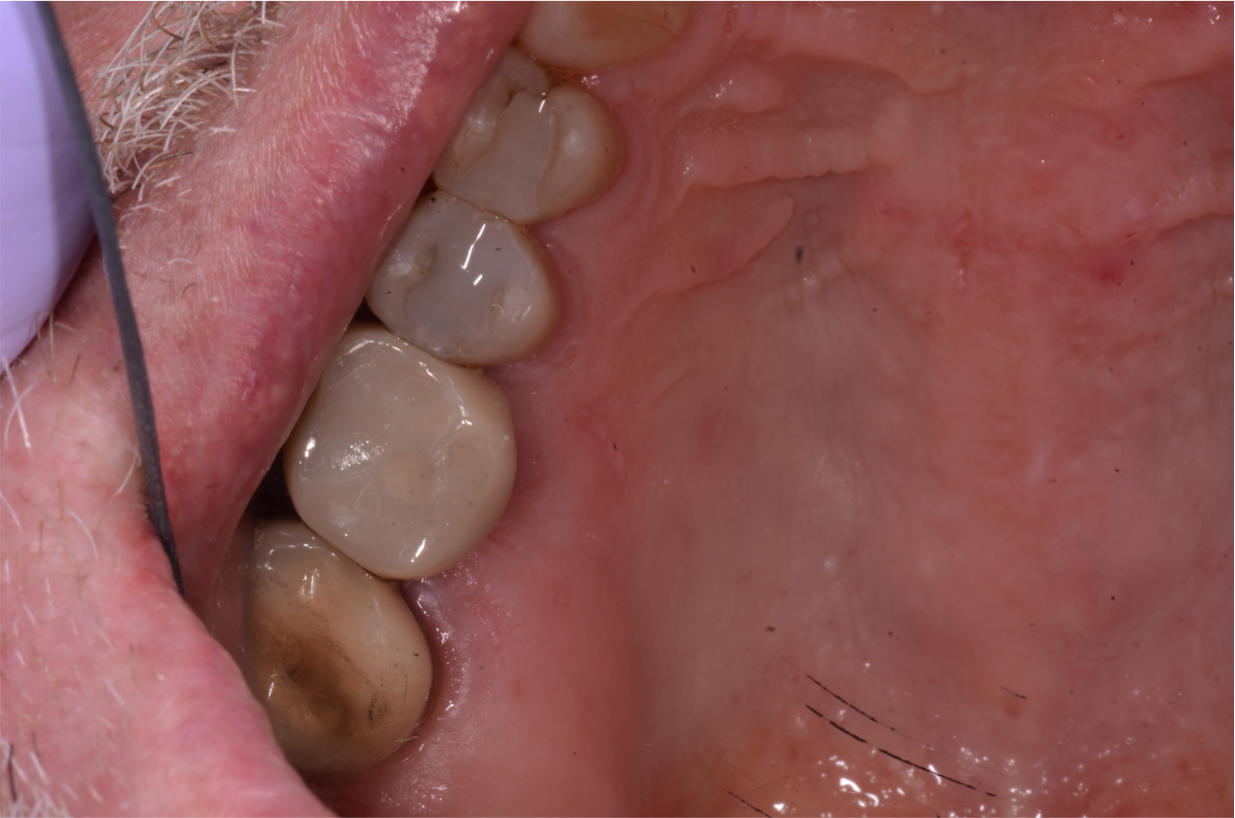

Fig 26. Abutment and crown assembly reseated in mouth.

Figure 26

With a guide pin in position to prevent any cement from getting into the screw-access hole, the custom abutment was seated on the implant analog in the model, and the PFM restoration was cemented onto it with a non-eugenol resin-based implant cement (Figure 25). Proper seating was confirmed, and the contacts were adjusted. The restoration was removed from the implant analog, excess cement was cleaned off, the guide pin was removed, and the cement-retained restoration was then seated on the implant in the mouth and tightened to 35 Ncm. Although it is easier to cement the PFM restoration to the custom abutment on the model, alternatively, it is possible to insert the custom abutment in the mouth and cement the crown to it, making sure that the orientation is correct and the contacts are optimal. The abutment and crown assembly is then removed for cement removal and then reseated in the mouth (Figure 26).